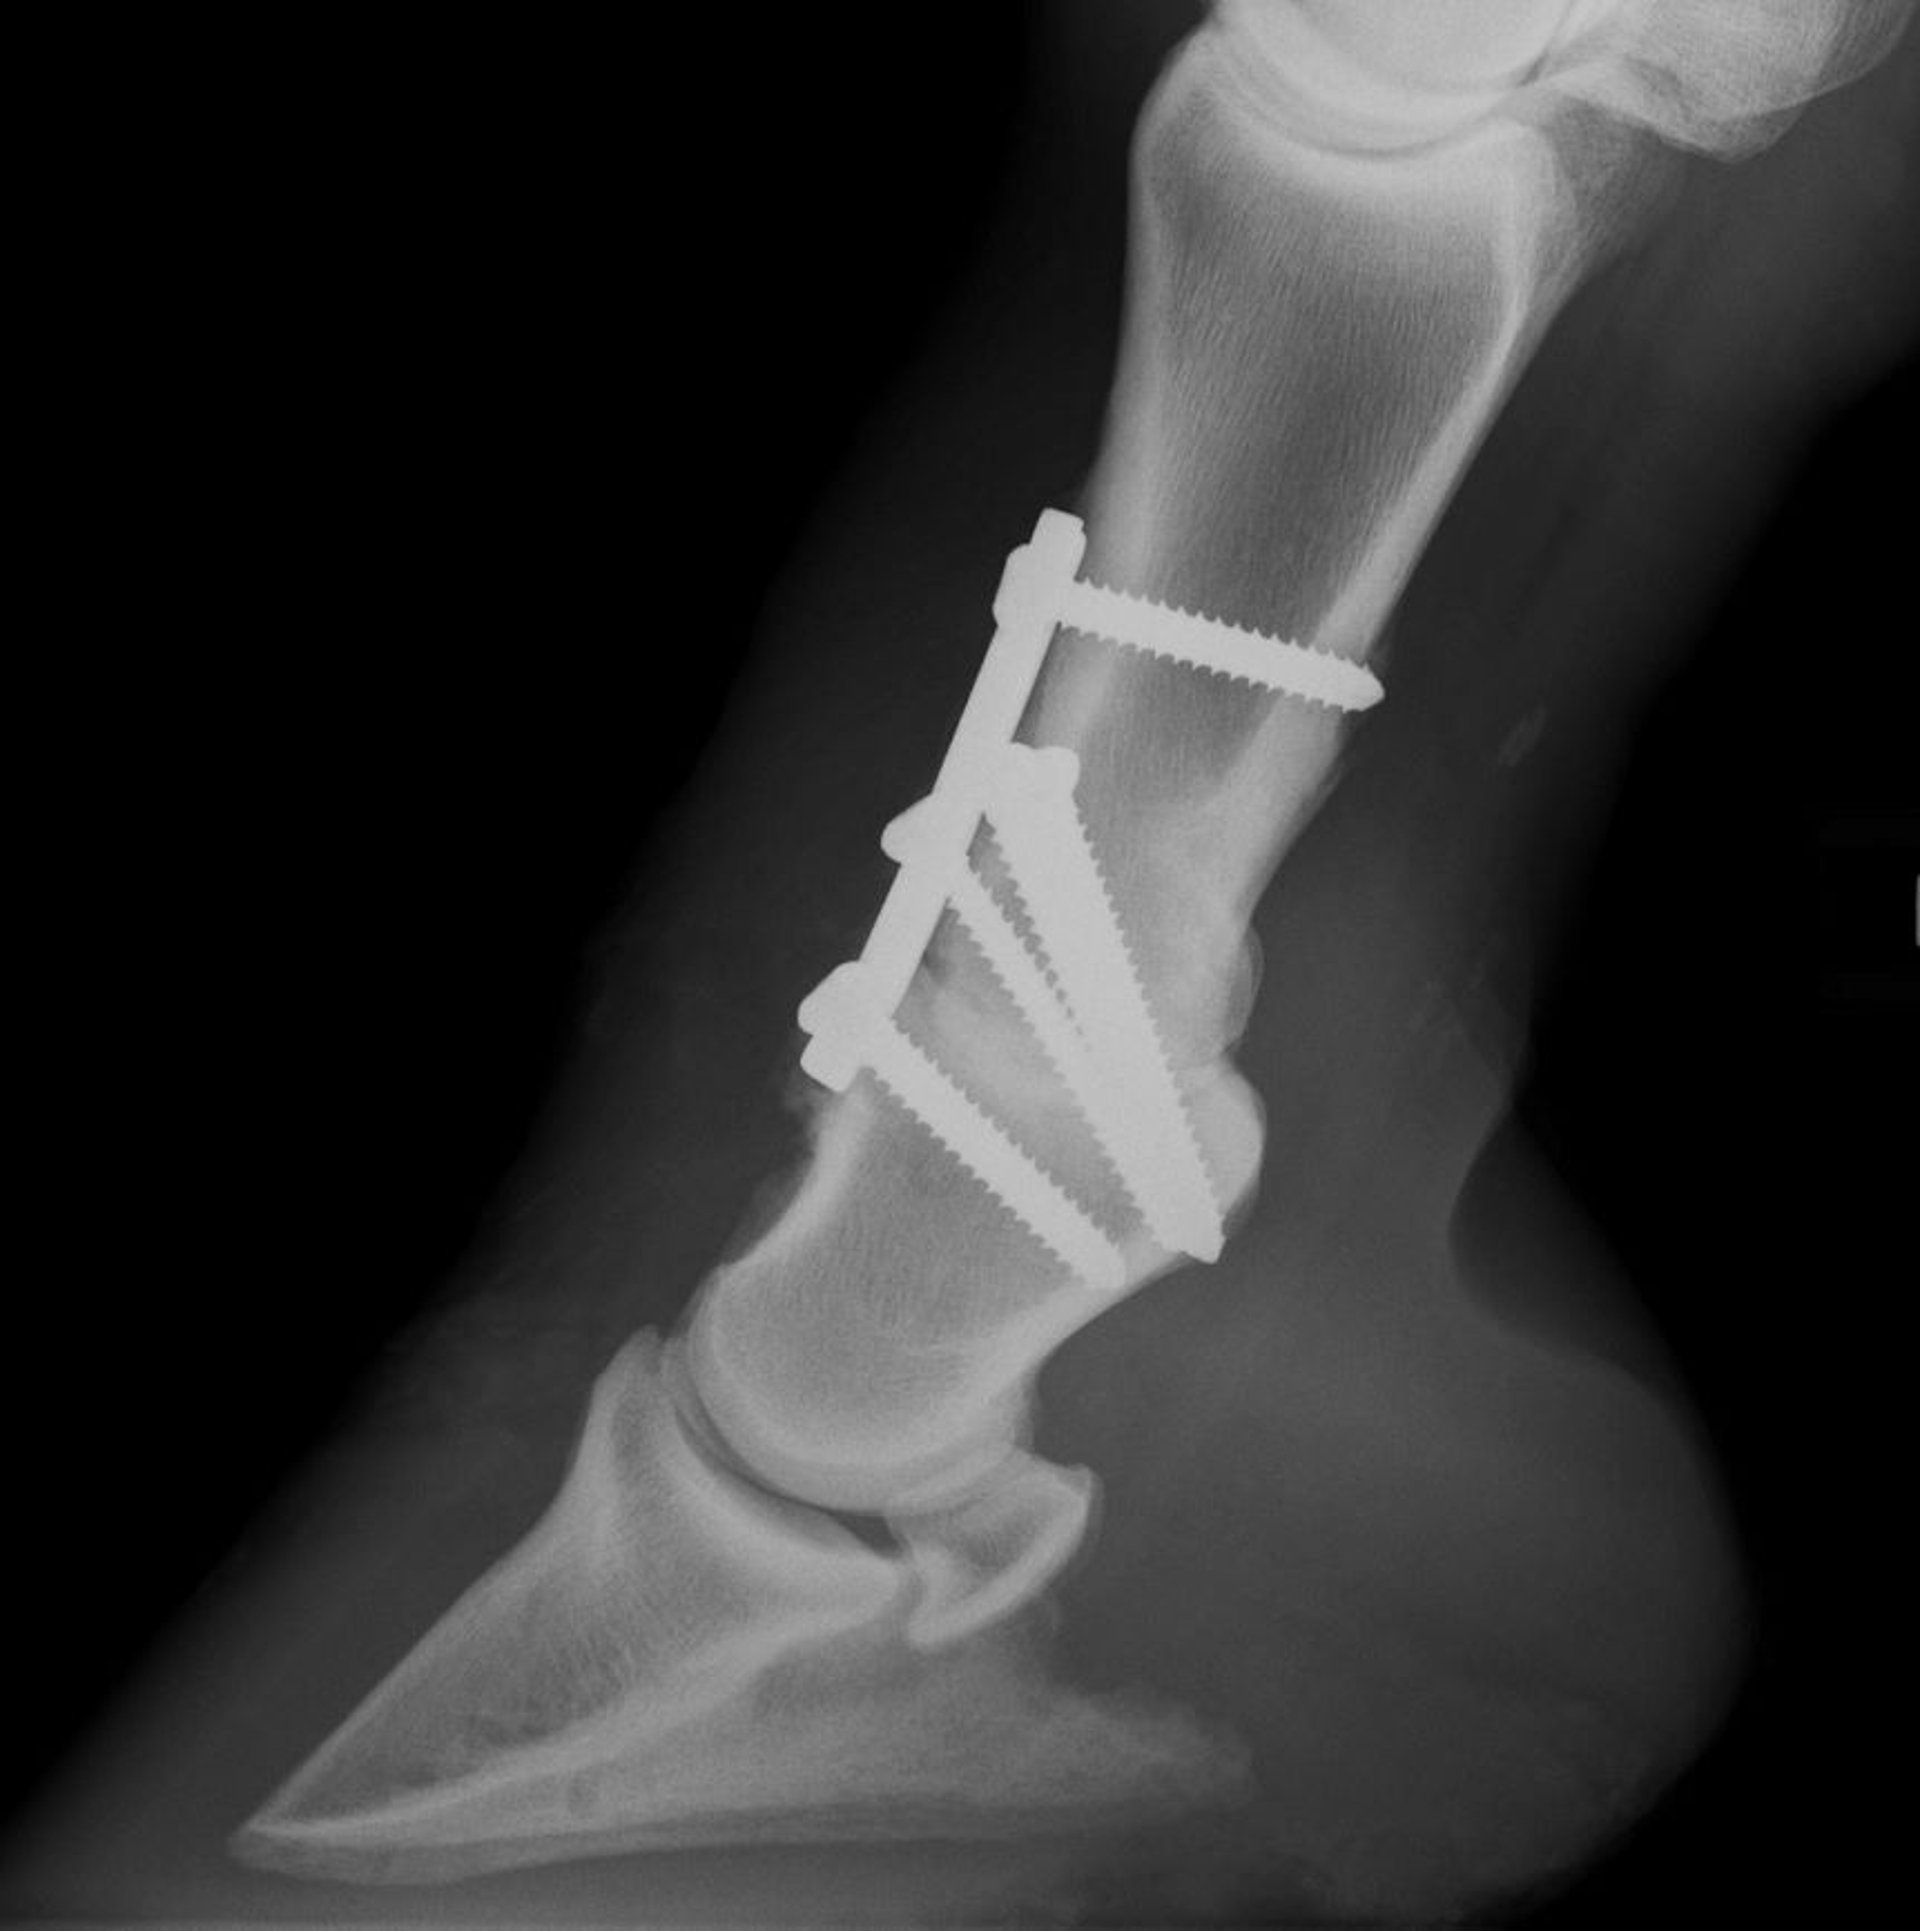

Radiografía de artrodesis de la cuartilla en caballos

Imagen radiográfica lateromedial que muestra una artrodesis de la cuartilla en un caballo mediante la combinación de una placa dorsal y tornillos de compresión.

Cortesía del Dr. Matthew T. Brokken.